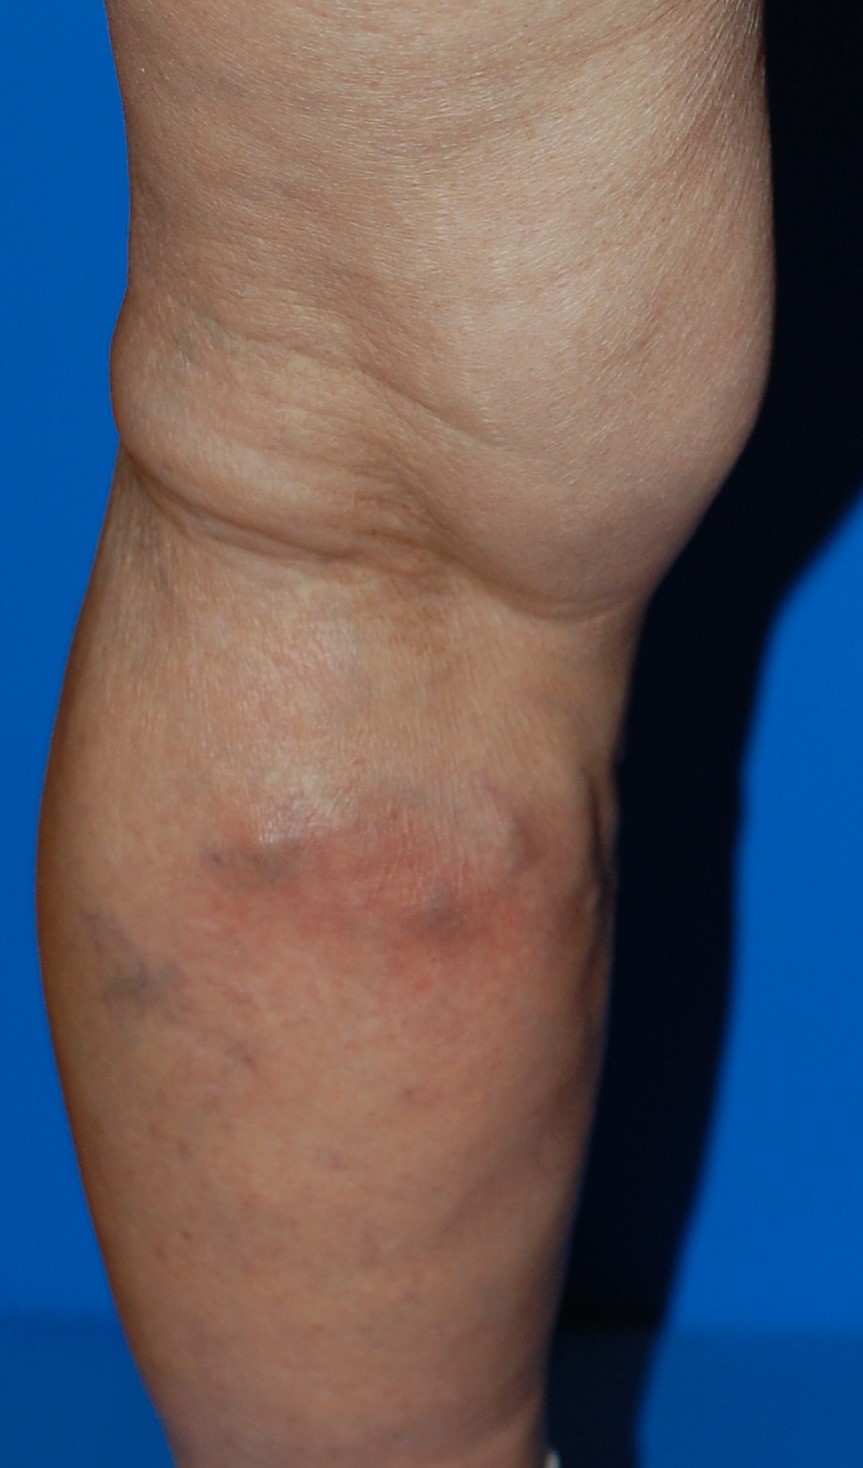

血栓性静脈炎

下肢静脈瘤がある方では、静脈瘤の中に血栓ができる「血栓性静脈炎」を起こすことがあります。

血栓性静脈炎は、単なる炎症で終わるとは限りません。

静脈瘤内に生じた血栓が深部静脈へ流れ込むと、いわゆるエコノミークラス症候群(肺塞栓症)へ発展する可能性もあります。

こんな症状があれば要注意

足の血管がボコボコと浮き出ている方で、

- ある日突然、足が赤く腫れてきた

- 押すと強い痛みがある

- 触ると熱っぽい

このような症状が出た場合、血栓性静脈炎の可能性が高いと考えられます。